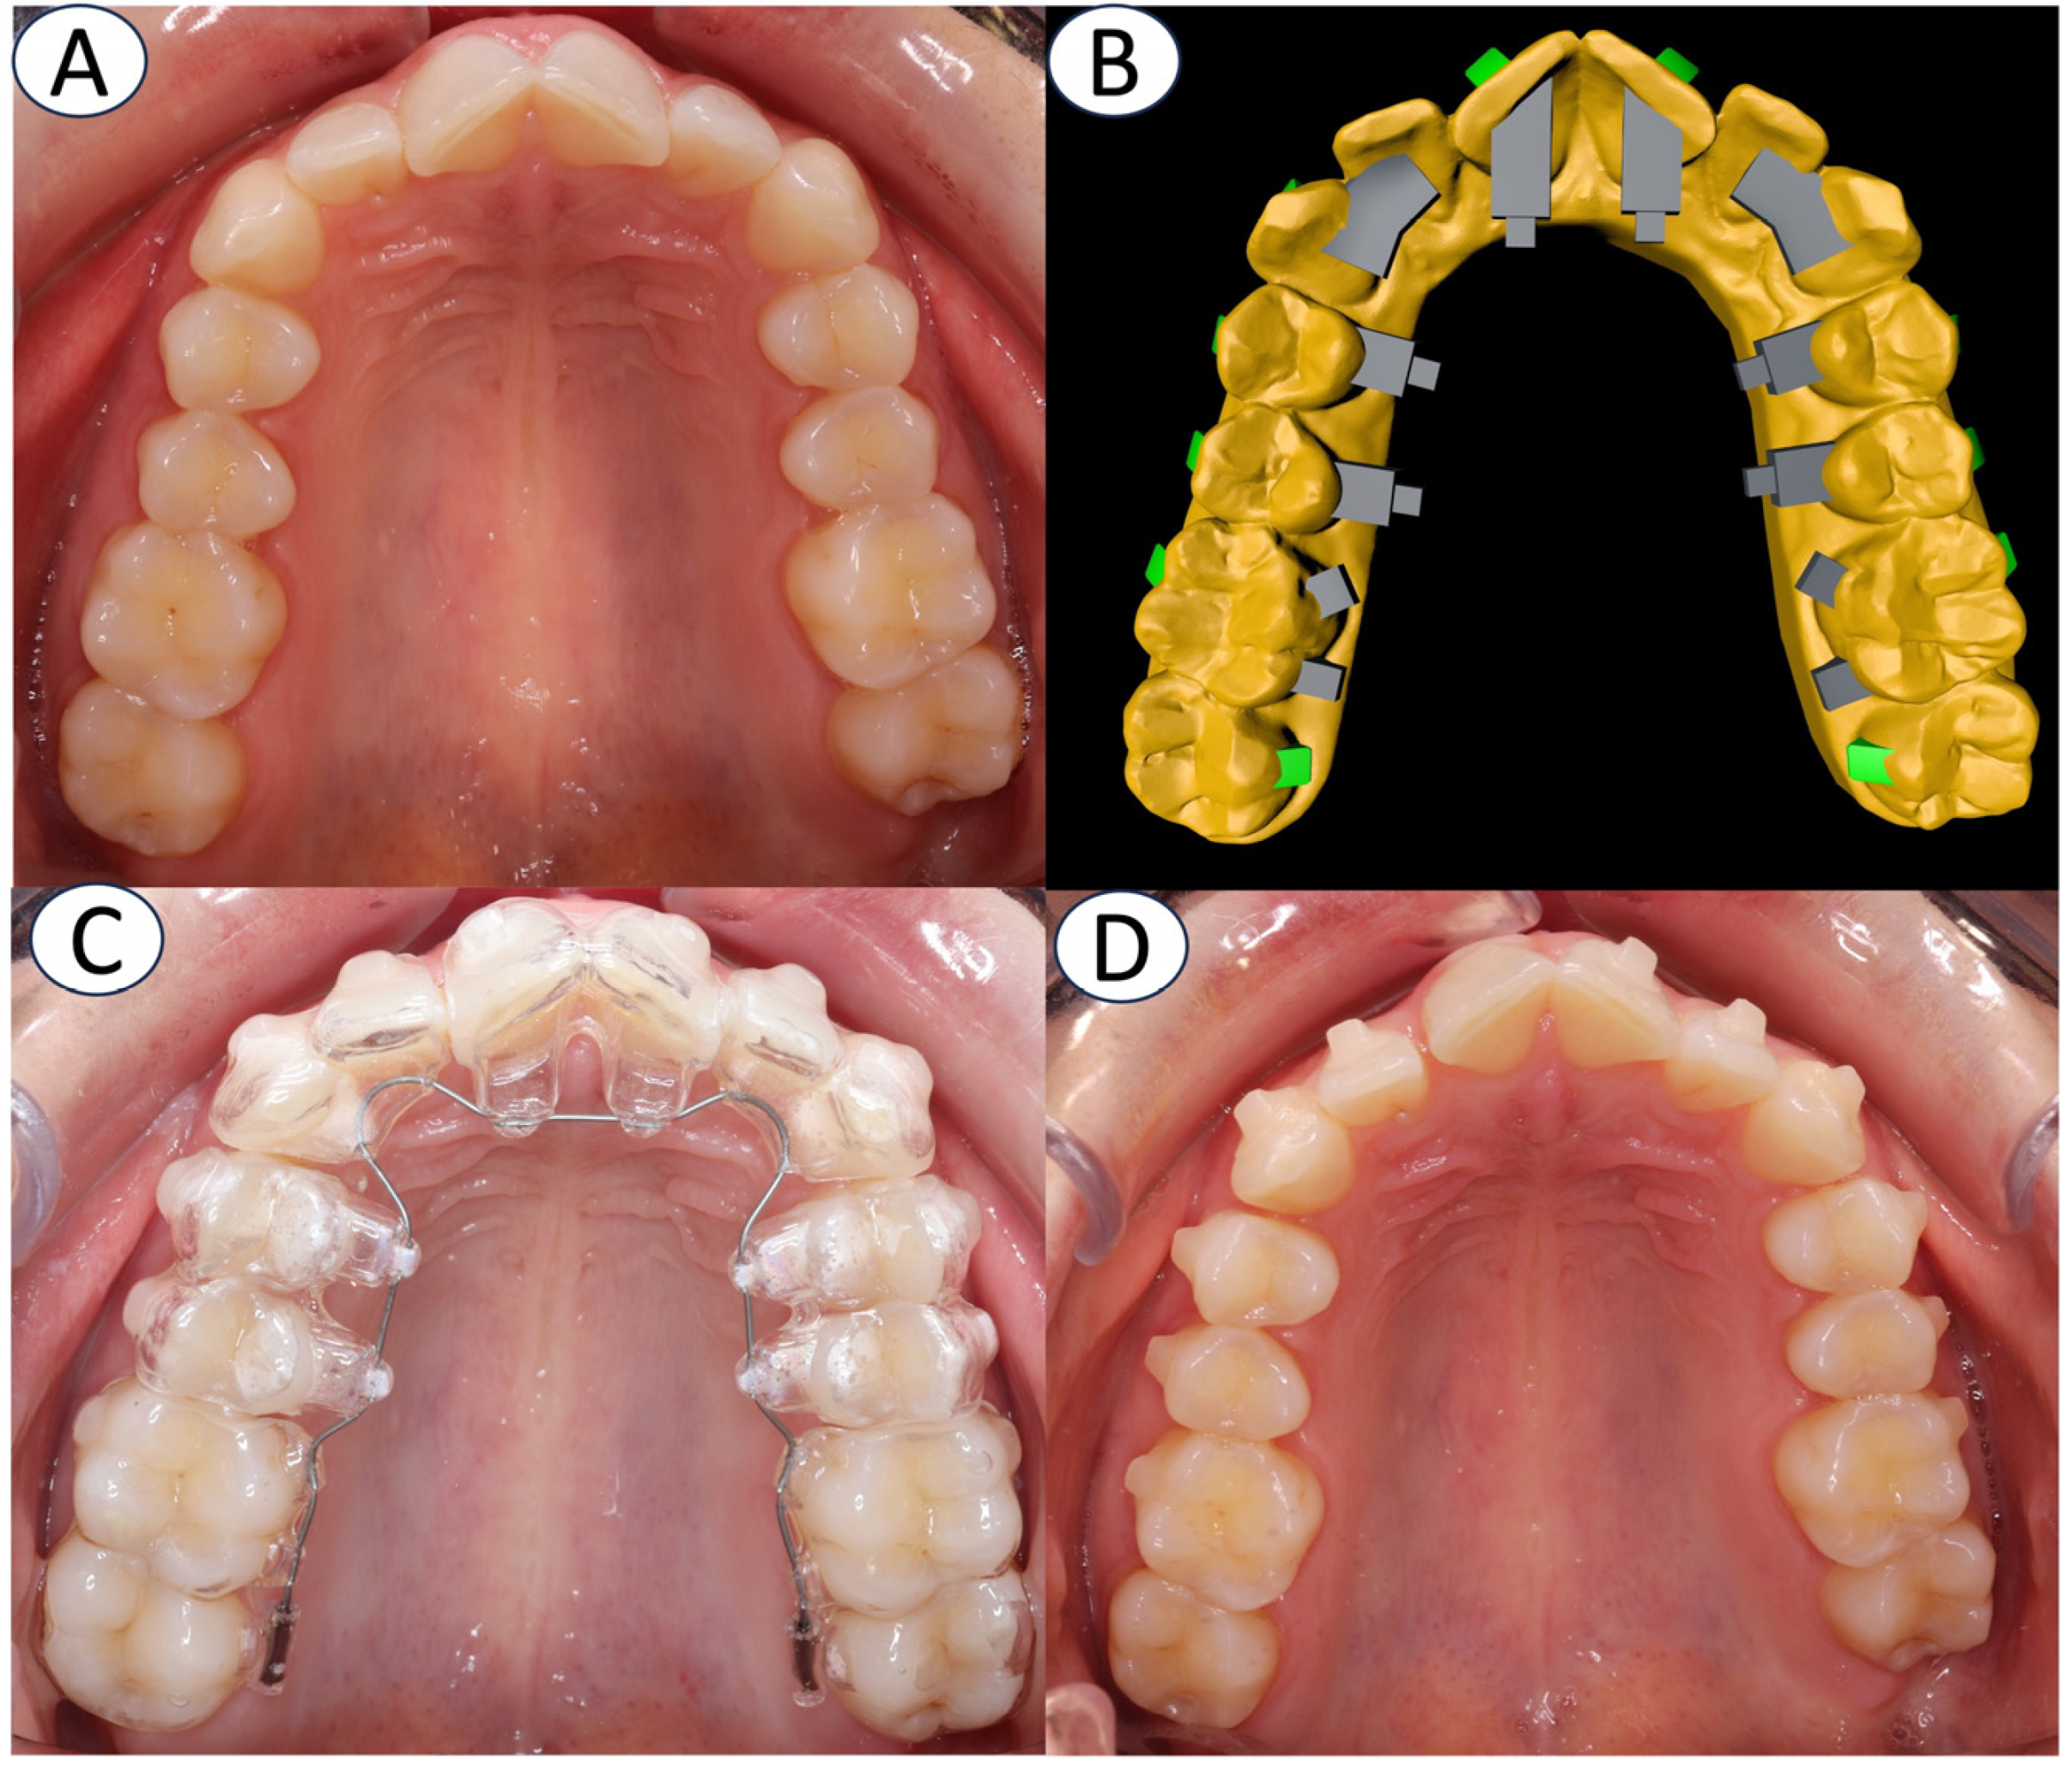

2. Materials and Methods

2.1.1. GT Group

2.1.2. Clear Aligner Group